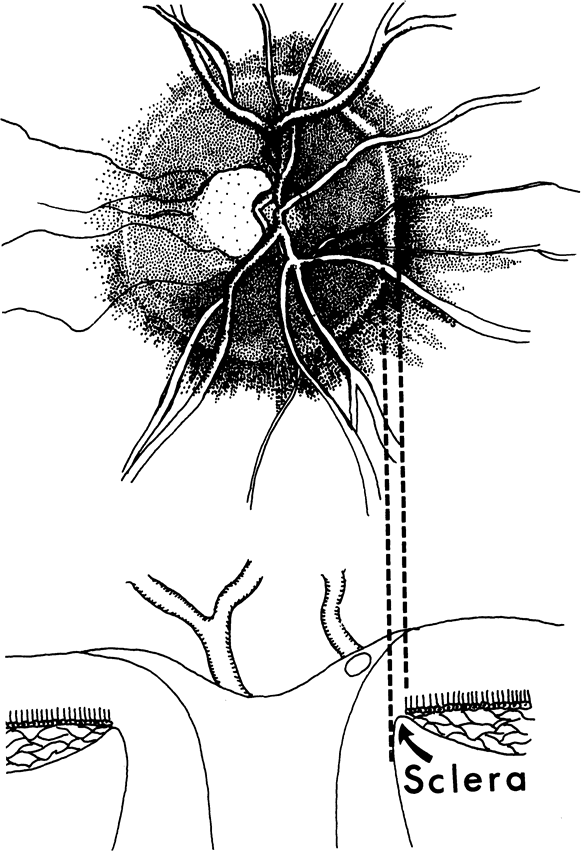

The approximately 1 to 1.5 million axons that form the optic nerve arise from the retinal ganglion cells and course toward the optic disc in a well-known pattern (Fig. 1). From the nasal retina the fibers take a straight course toward the disc. Axons originating temporal to the fovea arc around the macula to enter the upper and lower poles of the optic nerve head. The macula fibers pass directly to the temporal quadrant of the disc in the papillomacular bundle.

Fig. 1. Fundus photograph shows the normal pattern of the retinal nerve fiber layer. (Courtesy of P. Juhani Airaksinen, MD).